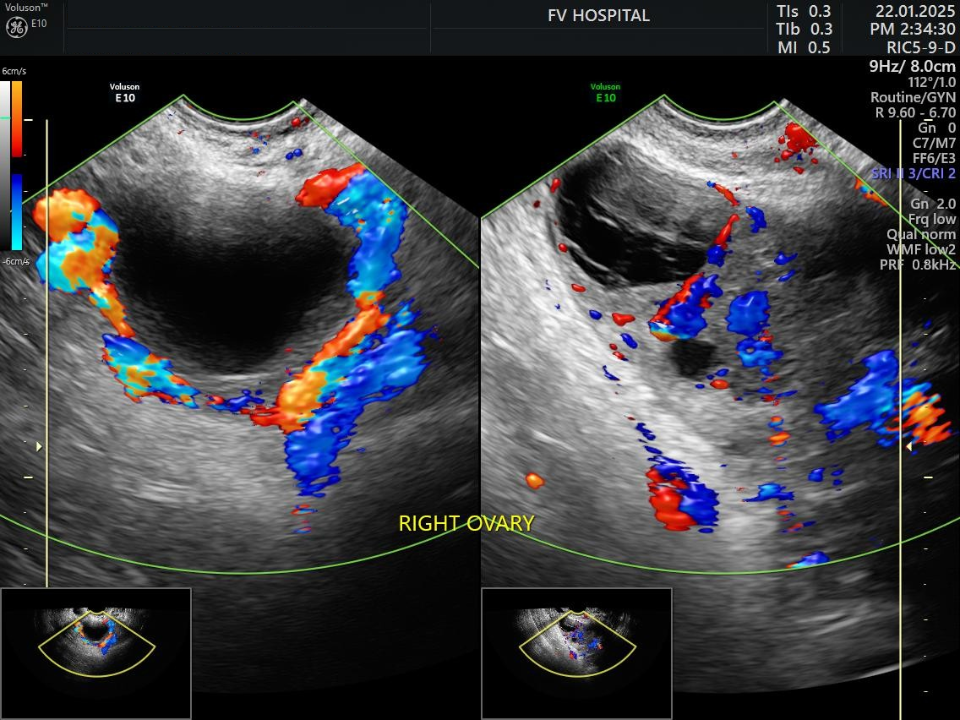

Chị X.A., 30 tuổi, đến Bệnh viện FV với triệu chứng đau nhẹ vùng hố chậu phải. Sau 24 giờ, cơn đau tăng đột ngột, kèm buồn nôn, nôn ói. Siêu âm cho thấy buồng trứng phải phình to gần gấp đôi. ThS.BS Võ Triệu Đạt lập tức yêu cầu hội chẩn liên chuyên khoa với các chuyên gia ngoại khoa và chẩn đoán hình ảnh. Kết luận sau hội chẩn cho thấy đây là tình trạng xoắn phần phụ buồng trứng ở bệnh nhân mang thai 5–6 tuần.

Hình siêu âm tái khám sau 1 tuần: bên trái buồng trứng xoắn, bên phải buồng trứng đã được tưới máu lại bình thường sau phẫu thuật. (Ảnh: FV)